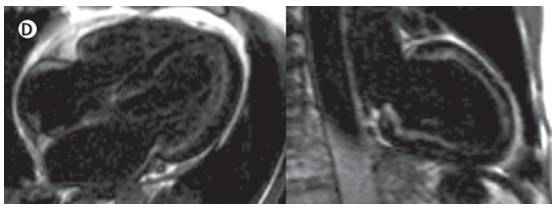

心肌活检

心脏MRI

◆心房扩张,心室增厚

◆镓造影剂延迟强化:弥漫或片状分布,与冠脉分布无关联,心内膜下,心房心室均可见

◆T1 mapping技术:心脏细胞外容积(excellular volume)扩大

◆可评估淀粉样变负担,对预后判断有价值